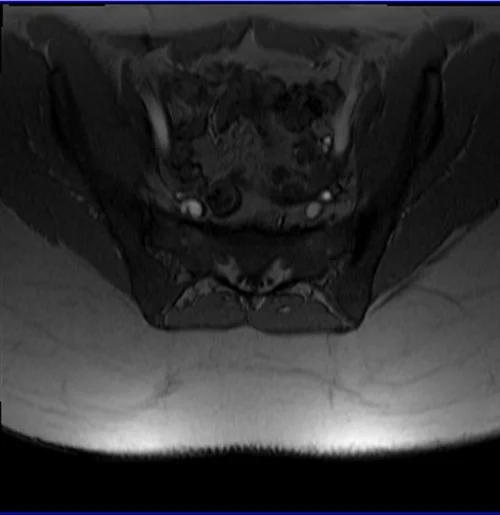

mri sij loc 1 - MRI